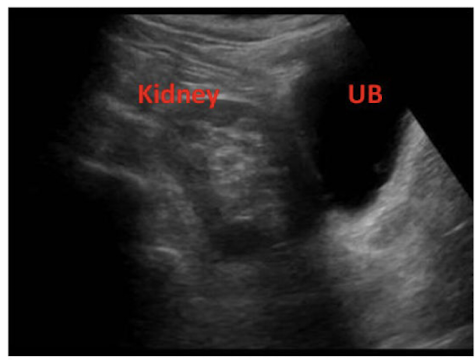

What is this image showing?

More of the liver is shown in this image so it is the ________ kidney

Right kidney is shown